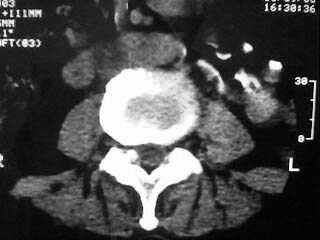

标题: CT15786:腰痛,腿麻三个月

f,64。腰痛,腿麻三个月

是黄韧带钙化吗

腰椎退行性变;黄韧带钙化。

黄韧带增厚钙化

是!黄韧带钙化的诊断没问题!!